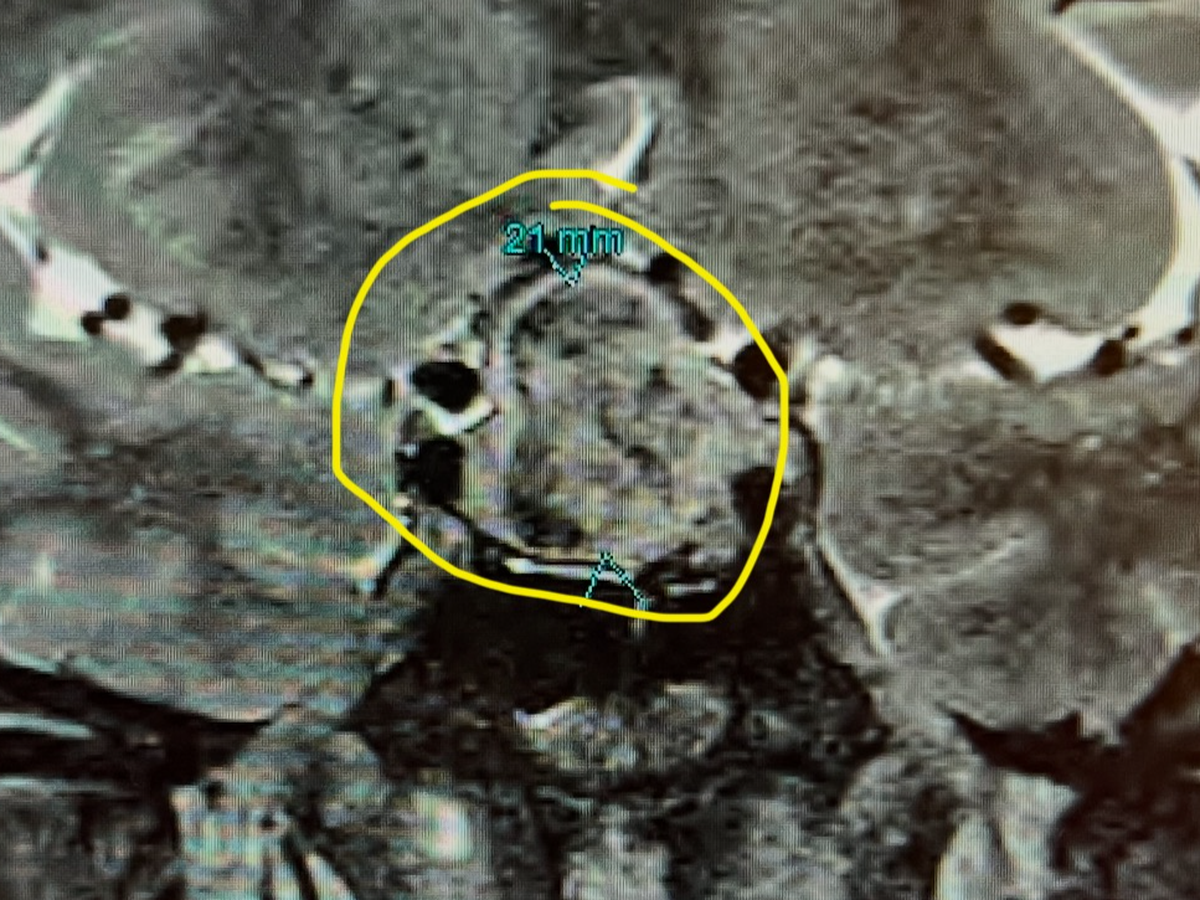

My name is Melissa. I was recently diagnosed with a Pituitary Gland tumor, which I had removed on Monday, the 10th of February. I have now been diagnosed with Acromegaly. As far as I understand, I will battle this for the rest of my life. I will need hormone replacement therapy to do the job my Pituitary Gland can no longer do. I am not familiar with this process; however, I have heard from a few independent people that it is time-consuming to get approved and expensive even when you do.